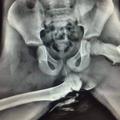

Rentgenski posnetek noge na armaturki

Pazljivo

Imela je noge na armaturki, takšne so posledice

Priljubljena navada marsikaterega sopotnika ima lahko grozljive posledice.